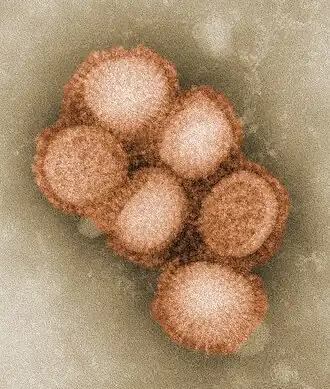

| Ampliação da estirpe de gripe A H1N1, responsável pela gripe espanhola em 1918 e pela gripe suína em 2009. | |

A gripe propaga-se globalmente em ciclos sazonais de epidemias, as quais provocam anualmente entre três e cinco milhões de casos graves da doença e entre 250 000 e 500 000 mortes,[14] número que pode ascender a milhões em anos de pandemia. Ao longo do século XX ocorreram três pandemias de gripe, cada uma delas provocada pelo aparecimento de uma nova estirpe do vírus em seres humanos, e responsáveis pela morte de dezenas de milhões de pessoas. Em muitos casos, as novas estirpes de gripe aparecem quando um vírus já existente se propaga para o ser humano a partir de outra espécie animal, ou quando uma estirpe humana recolhe novos genes de um vírus que só infeta aves ou suínos. Uma estirpe aviária denominada H5N1 levantou algumas preocupações em relação a uma nova pandemia de gripe em finais da década de 1990, mas não chegou a evoluir para uma forma de fácil contágio entre o ser humano.[15] Em abril de 2009 ocorreu uma pandemia de uma nova estirpe que combinava genes da gripe humana, aviária e suina, denominada H1N1 ou gripe suína.[16]

- H1N1, que provocou a gripe espanhola em 1918, gripe russa de 1977 e a gripe suína em 2009

O surto mais conhecido e mortífero foi a pandemia de gripe espanhola (tipo A e subtipo H1N1, ocorrida entre 1918 e 1919. Não é possível determinar com precisão o número de mortos, mas as estimativas apontam entre 50 e 100 milhões de pessoas.[164][165][166] Em Portugal terão morrido cerca de 120 mil pessoas.[167] Esta pandemia foi descrita como o "maior holocausto médico na História" e pode ter sido responsável pelo mesmo número de mortos da Peste Negra.[161] Este número de mortes foi provocado por uma taxa de infeção extremamente elevada de 50% e da extrema gravidade dos sintomas, os quais se suspeita terem sido provocados por tempestades de citocinas.[166] De facto, os sintomas de 1918 foram tão atípicos que inicialmente a gripe foi diagnosticada como dengue, cólera ou febre tifoide. Uma das principais complicações foi a hemorragia das mucosas, sobretudo do nariz, estômago e intestino, ocorrendo também hemorragias do ouvido e da pele.[165] A maioria das mortes deveu-se a pneumonia bacteriana, uma infeção secundária provocada pela gripe, embora o vírus também tenha sido responsável por mortes diretas ao provocar hemorragias e edema pulmonar.[168]